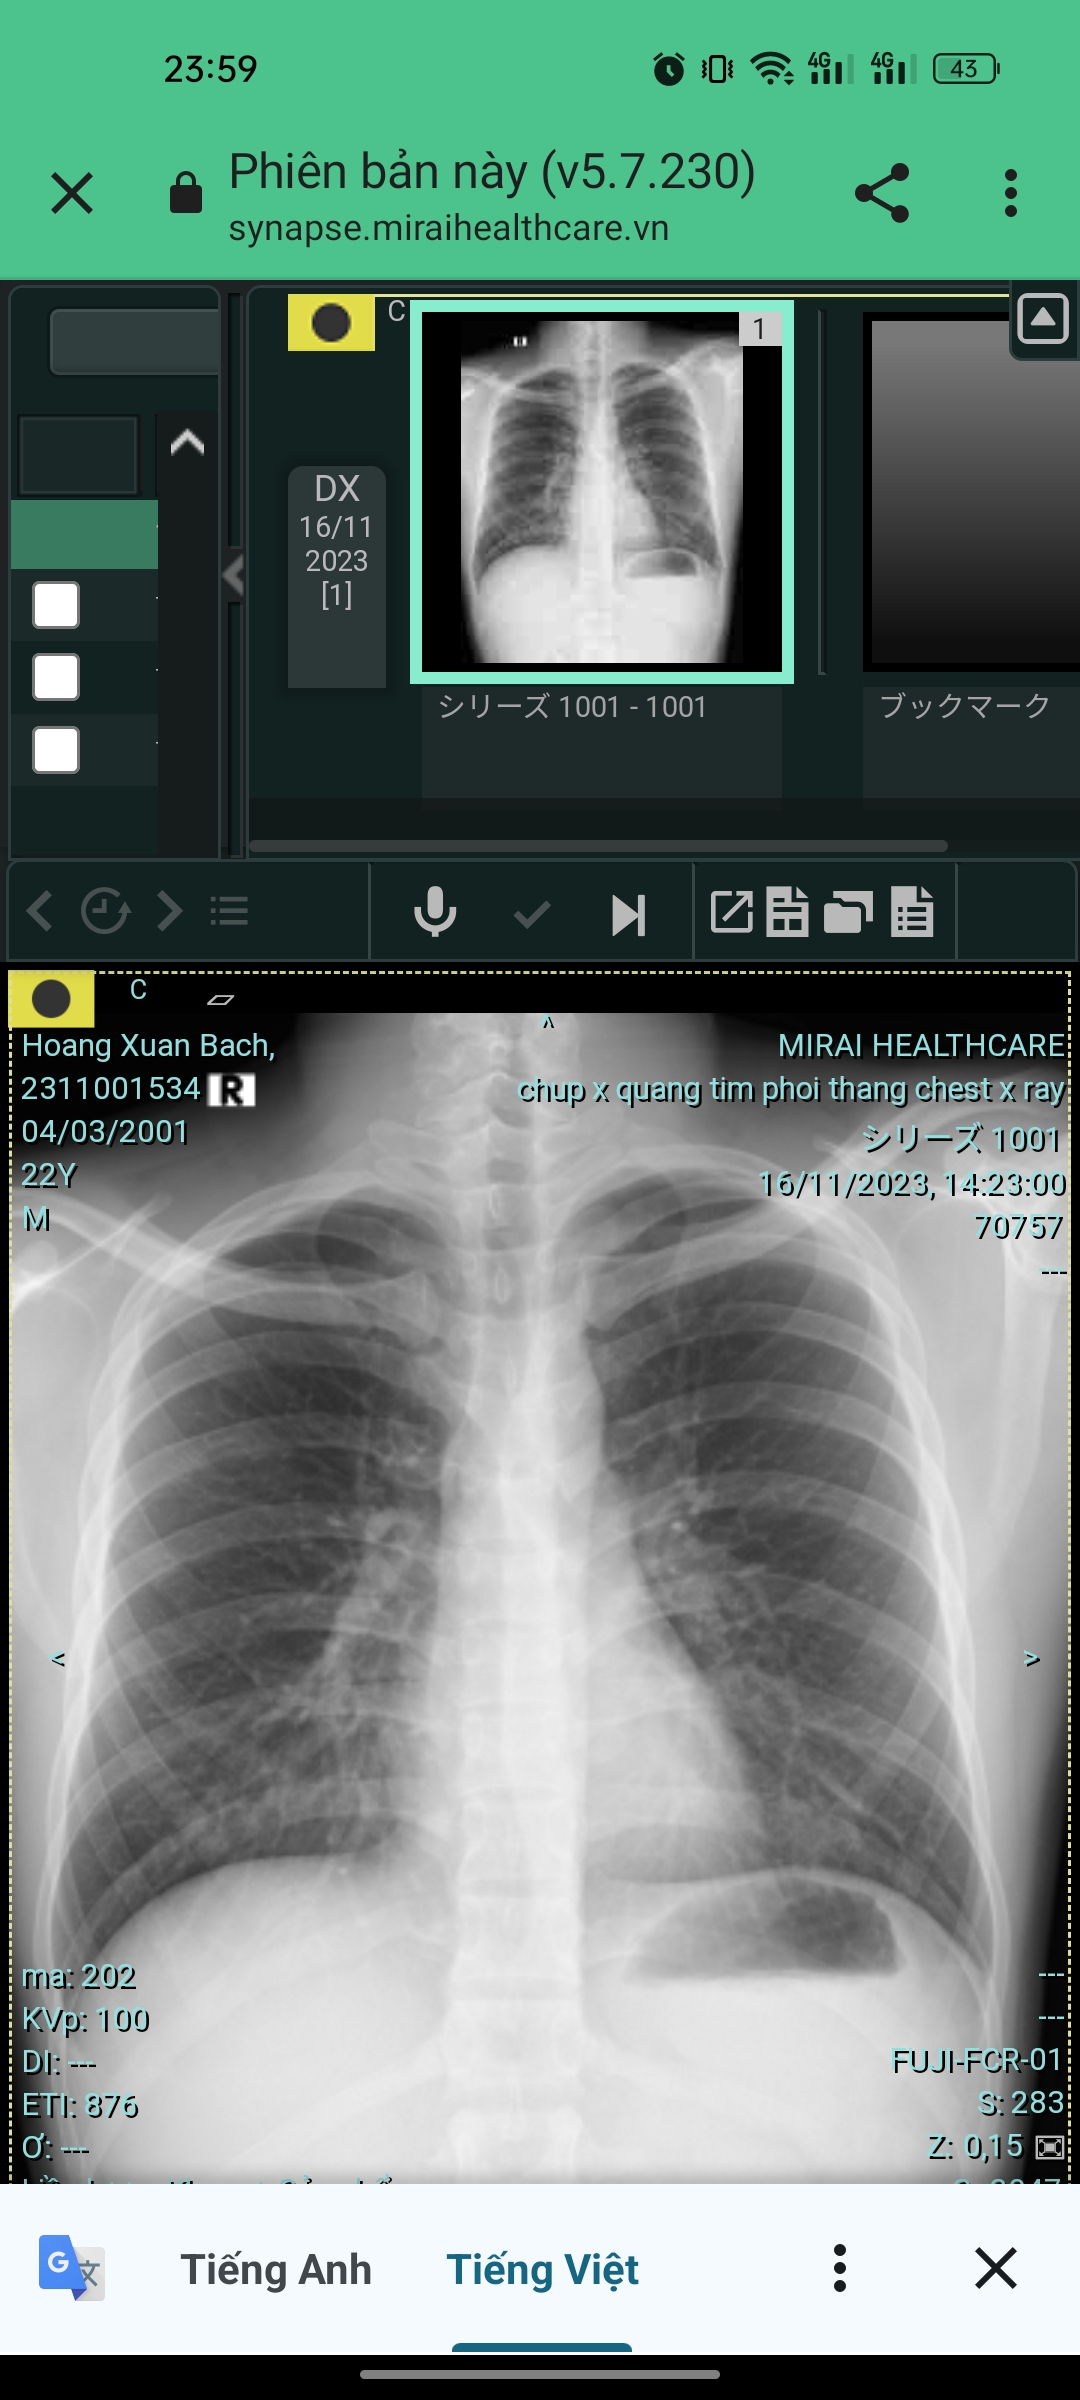

Cháu thi hoảng hắt xì hơi, hoặc cử động ( Vd : Gồng ngực ) thì thấy đau ngực phần bên trái. Sờ vào ngực thì thấy có cái gì như sợi dây thần kinh hay sợi cơ gì đó . Đi chụp thì kết luan mọi thứ bình thường . Thì không biết tình trạng của cháu là như nào ạ . Dưới là ảnh chụp X quang của cháu ạ